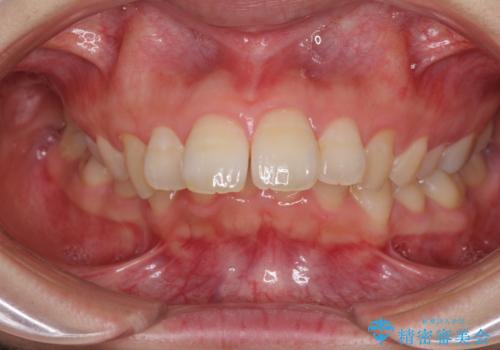

- 飛び出した上顎前歯を気にして来院された患者様です。

下顎は左右2番目の歯が2本欠損しており、上下前歯の前後的な位置は著しくずれている状態でした。

骨格的にも上顎骨が前突傾向にあり、極端な過蓋咬合になっていました。